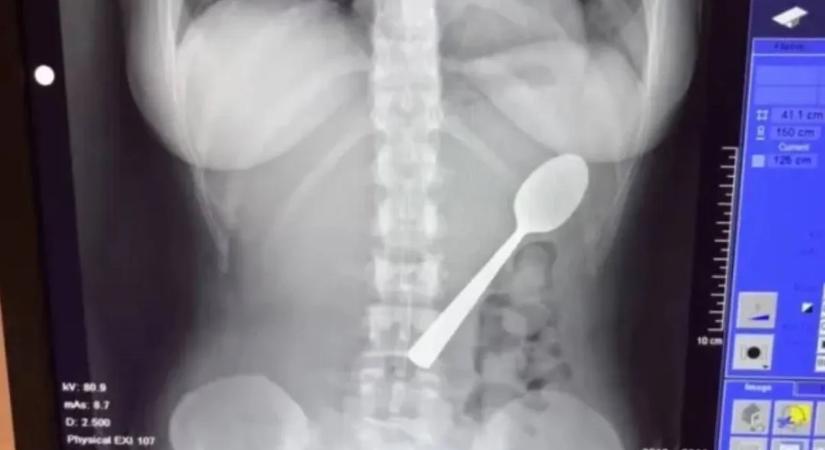

Magyar vizslája ugrott az ölébe, 17 centis kanalat kellett kiszedni a nő gyomrából